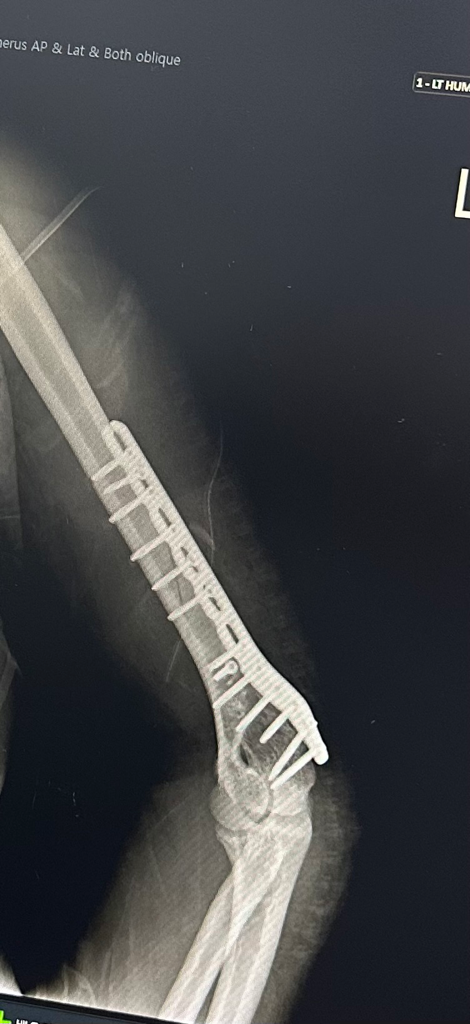

좌측 상완 분쇄골절 회복 속도

만 19세 저번주에 상완골 분쇄골절 되어 수술 했습니다

보통 회복하고 플레이트 빼는 시기가 1년 정도라는데

아직 젋으니 잘 자고 영양 잘 챙겨 먹으면 더 빨리 회복되어 플레이트를 몇개월 더 일찍 제거할수도 있나요?? (웨이트 했었음)

플레이트는 무조건 제거할겁니다

• 1번 째 사진

수술도 어려운 부위인 만큼 제거술도 쉽지는 않습니다.

골절치유가 완료된 상태라면 6개월 정도부터는 금속판 제거가 가능하시기 때문에 재활에 집중하시는 것이 좋겠습니다.

• 젊고 건강하며 치료를 잘 받으면 회복 속도가 빠를 수는 있지만 수 개월이나 빨리 제거를 하는 것은 현실적으로 가능성이 매우 낮아 보입니다.